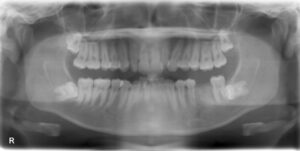

下顎6本欠損症例

BEFORE AFTER 60歳女性/下顎6本欠損/インプラント埋込手術 【治療内容】 歯周病の進行が原因で下顎臼歯が6…